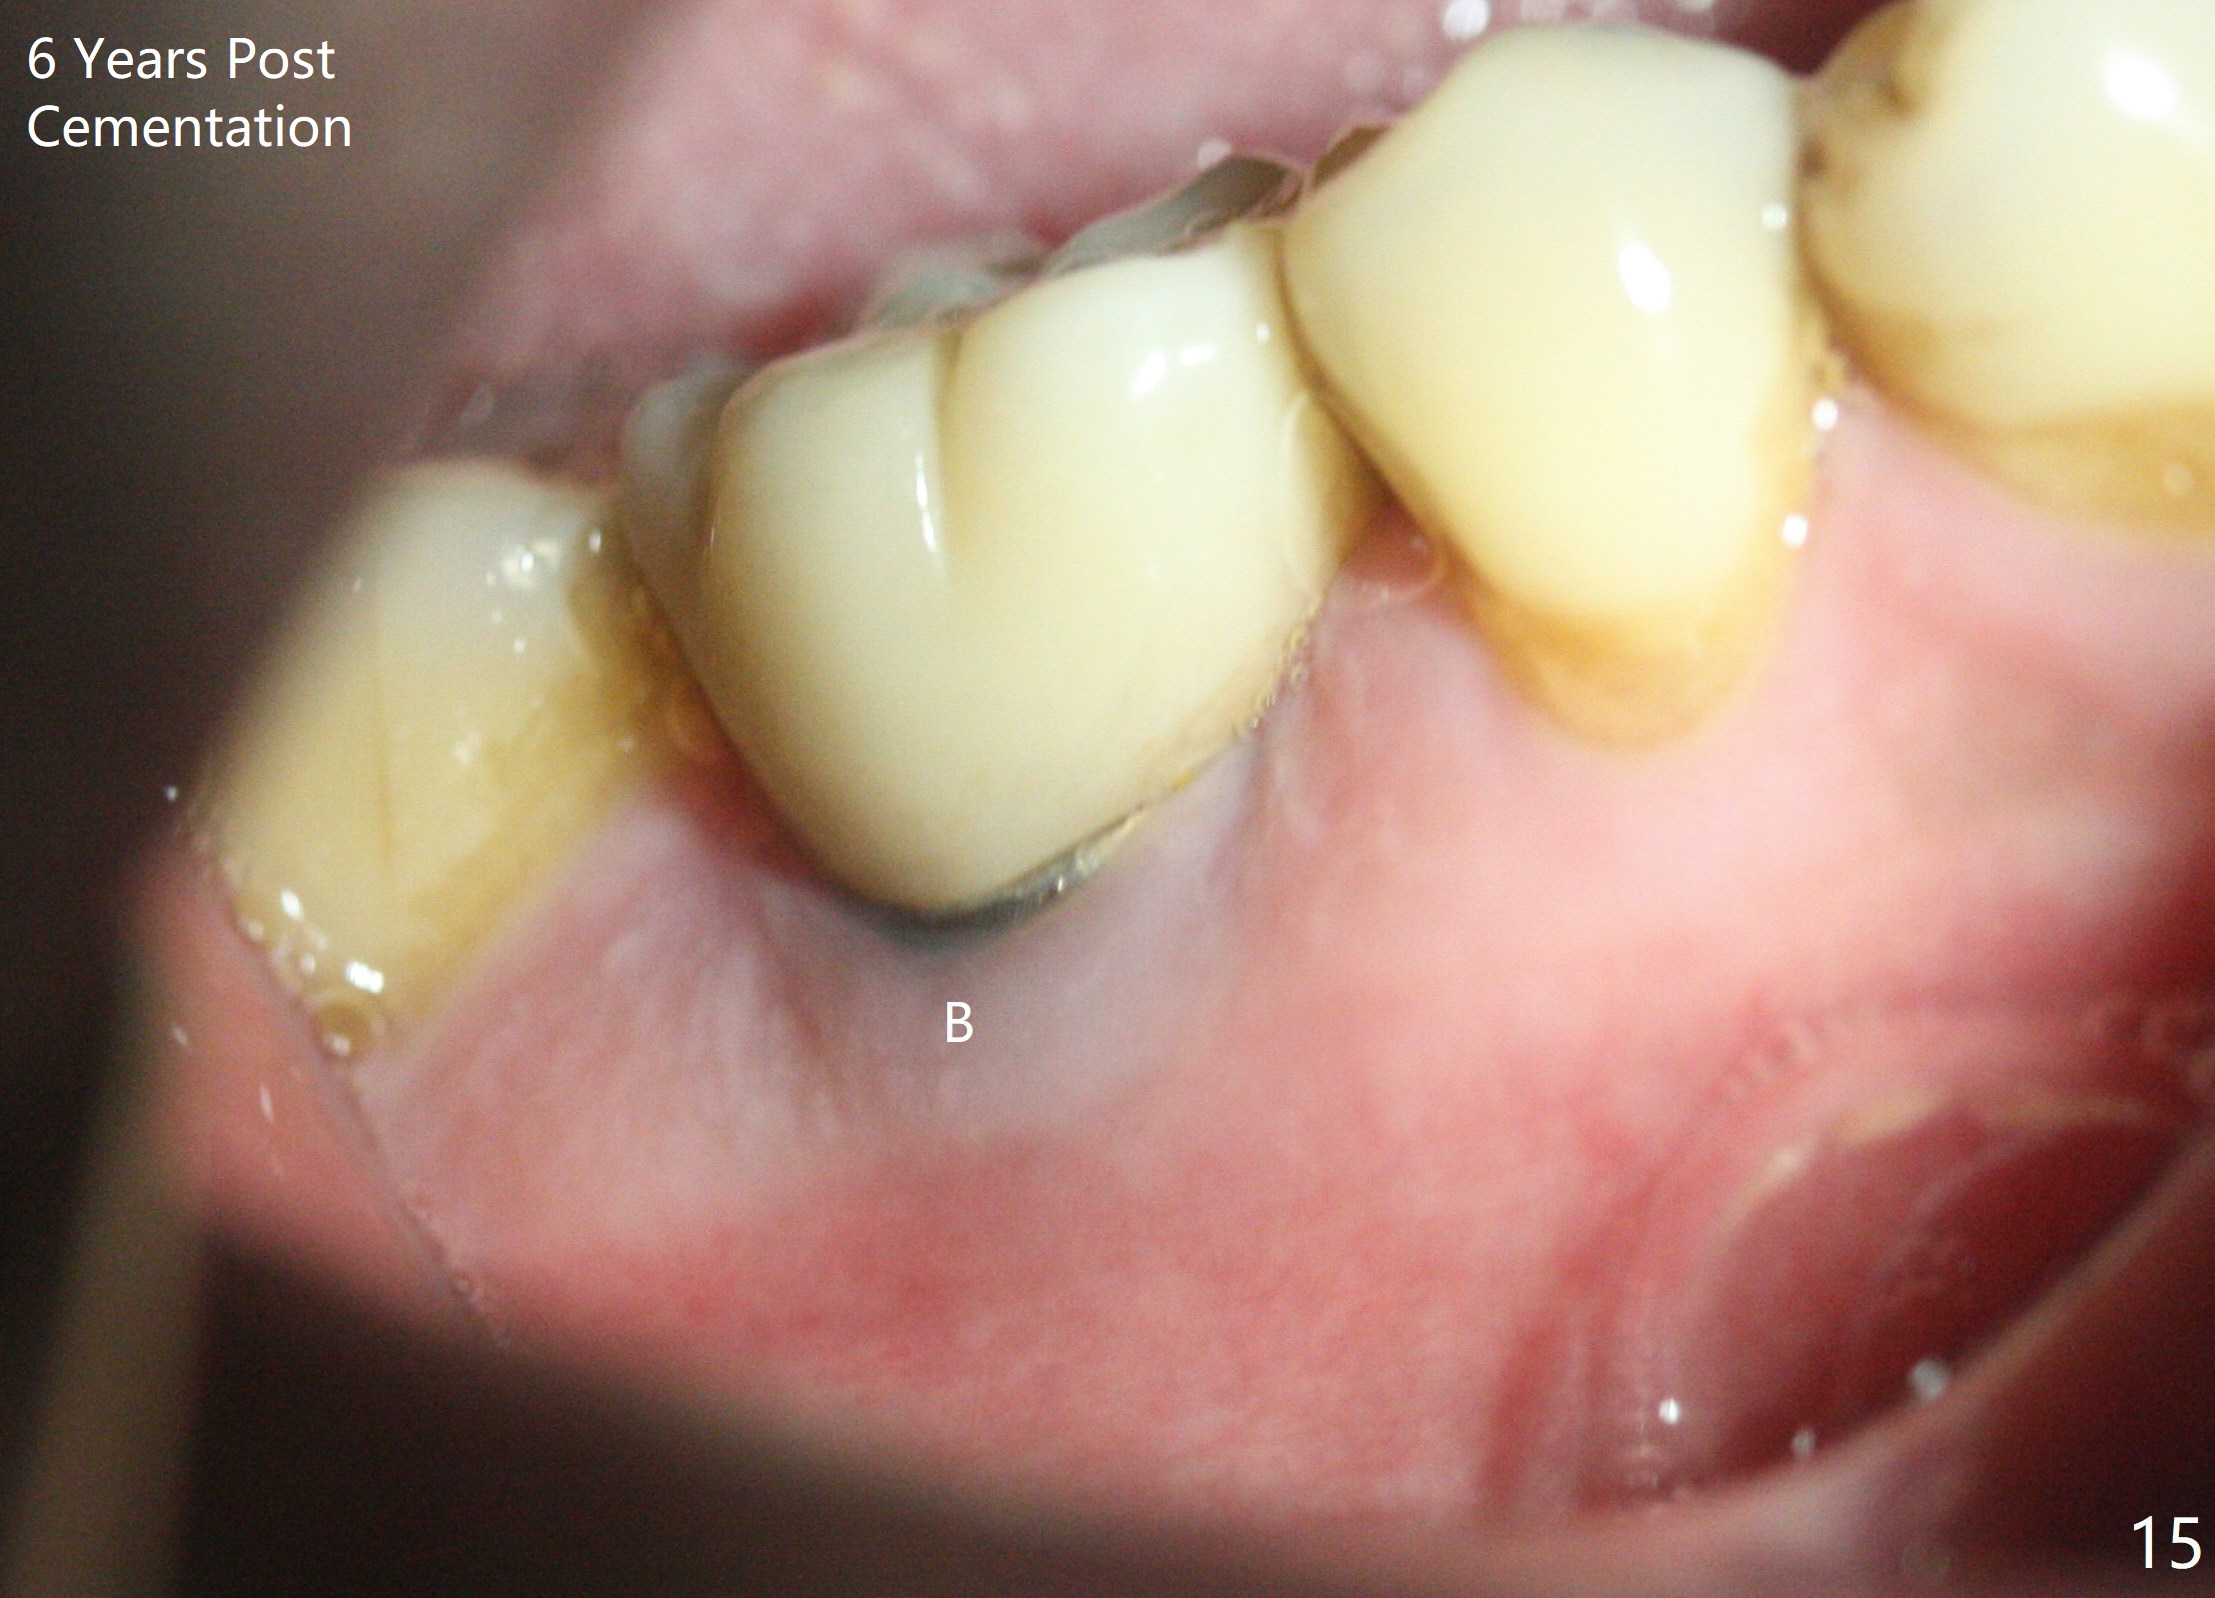

When a large implant is placed in a molar socket, one dimension of the remaining socket is small (buccolingual for lower, mesiodistal for upper). It is apparent that the mandibular buccal and lingual gingiva is relatively loose for the most time, the mesial and distal socket could be closed by suturing and perio dressing. The maxillary palatal gingiva is particularly thick and tough to be approximated. It appears necessary to develop a technique using an immediate provisional to close the socket or place an abutment. Cortex-like bone seems to have grown into the mesial thread spaces 3 years post cementation (Fig.13 <). The 7x17 mm implant was placed buccal (Fig.14 B). The slowly resorbed buccal plate seems to darken the buccal gingiva (Fig.15 B). The bone next to the implant is dense 6 years post cementation (Fig.16 *). The implant at 19 should be smaller and placed lingual.